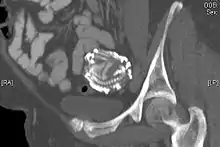

A lithopedion (also spelled lithopaedion or lithopædion; from Ancient Greek: λίθος "stone" and Ancient Greek: παιδίον "small child, infant"), or stone baby, is a rare phenomenon which occurs most commonly when a fetus dies during an abdominal pregnancy,[1] is too large to be reabsorbed by the body, and calcifies on the outside as part of a foreign body reaction, shielding the mother's body from the dead tissue of the fetus and preventing infection.

Lithopedia may occur from 14 weeks gestation to full term. It is not unusual for a stone baby to remain undiagnosed for decades and to be found well after natural menopause; diagnosis often happens when the patient is examined for other conditions that require being subjected to an X-ray study. A review of 128 cases by T.S.P. Tien found that the mean age of women with lithopedia was 55 years at the time of diagnosis, with the oldest being one-hundred years old. The lithopedion was carried for an average of 22 years, and in several cases, the women became pregnant a second time and gave birth to children without incident. Nine of the reviewed cases had carried lithopedia for over 50 years before diagnosis.[2]

According to one report there are only 300 known cases of lithopedia[3] recorded over 400 years of medical literature. While the chance of abdominal pregnancy is one in 11,000 pregnancies, only between 1.5 and 1.8 percent of these abdominal pregnancies may develop into lithopedia.[4]